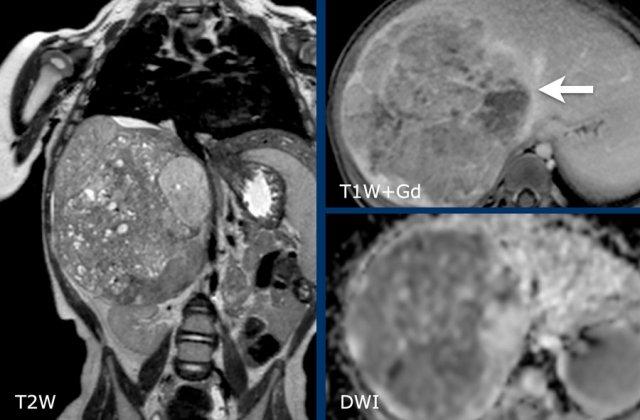

Ví dụ 1

Một bé gái ba tuổi có khối u thận trái và huyết khối khối u lớn trong tĩnh mạch thận và tĩnh mạch chủ dưới. Có di căn gan (phát hiện không thường gặp) và di căn phổi.

A. The tumor enhances less than the peripheral remnant of normal renal tissue (blue arrow). The left renal vein is open (yellow arrow). Solid parts of the tumor show diffusion restriction (white arrow)

U nguyên bào thận thường không đồng nhất, với tín hiệu giảm trên T1 và tín hiệu tăng trên T2. Các vùng hoại tử dạng nang thường hiện diện.

Tăng cường tín hiệu sau tiêm Gadolinium không đồng nhất và kém hơn so với sự tăng cường của nhu mô thận bình thường.

Các phần đặc của khối u sẽ cho thấy khuếch tán hạn chế. Xuất huyết thường gặp. Các vùng xuất huyết cũng sẽ cho thấy khuếch tán hạn chế, vì vậy hãy quan sát trên hình ảnh T1 để tìm dấu hiệu chảy máu.

MRI có thể hiển thị rõ ràng huyết khối u trong tĩnh mạch thận và tĩnh mạch chủ dưới, cũng như tình trạng hạch bạch huyết to. Phương pháp này cho phép đo lường khối u một cách chính xác và có thể lặp lại trong các lần khám ban đầu và theo dõi.